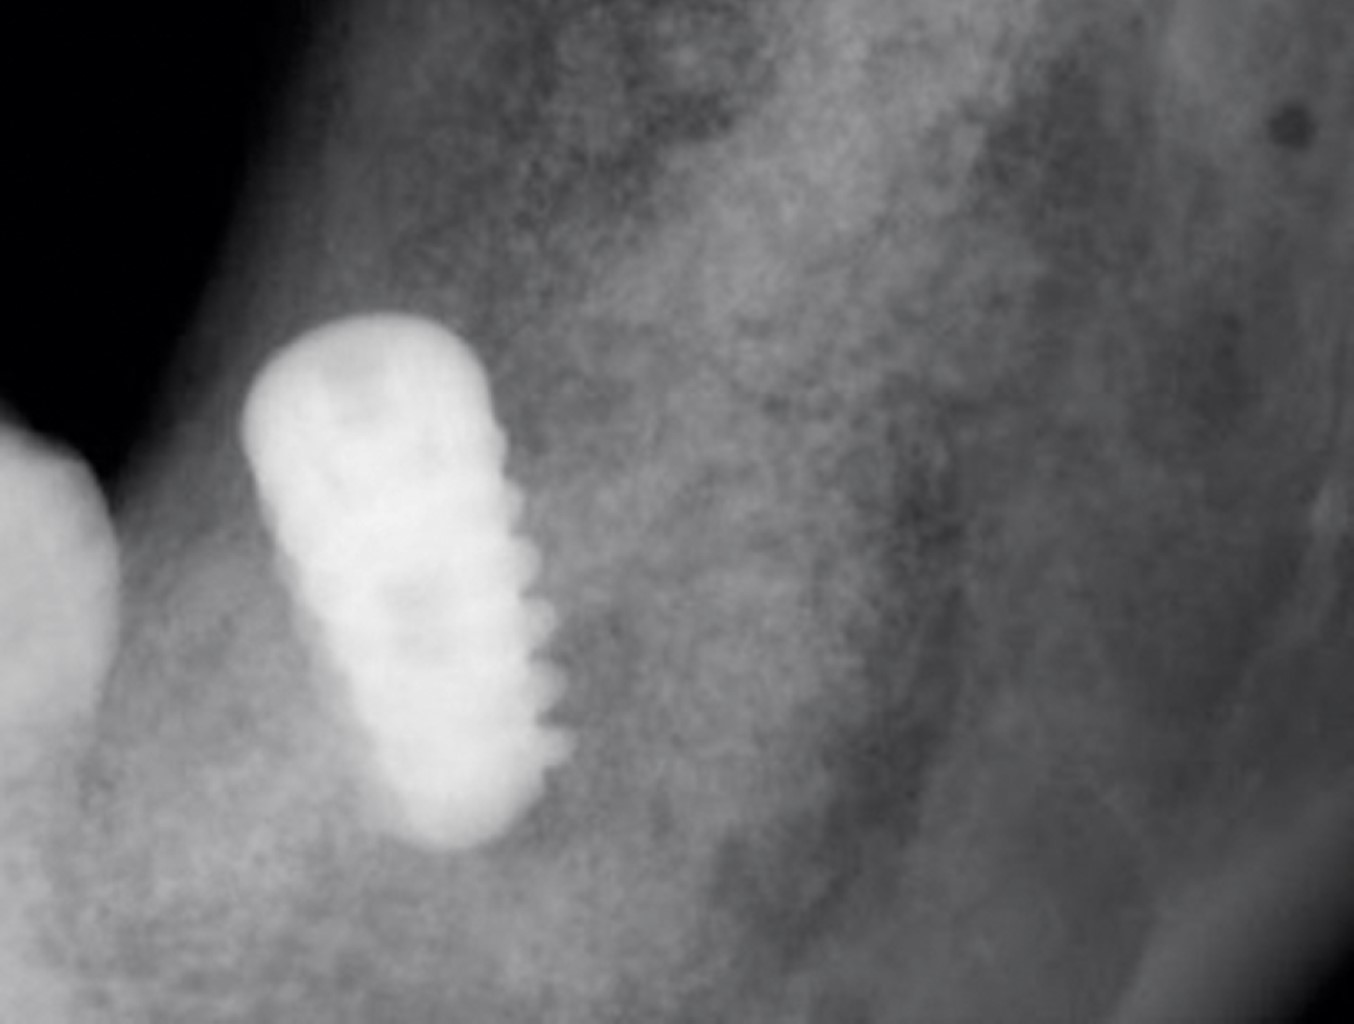

La radiografía panorámica permitió observar un área radiolúcida unilocular que se extendía a partir del cuerpo mandibular (Figura 1), desde la zona distal del primer molar inferior izquierdo hasta la parte mesial del segundo molar incluido, involucrando el canal del nervio inferior. El segundo molar inferior estaba incluido en la lesión y desplazado posterosuperiormente, así como desplazamiento basal del conducto dentario inferior. En la tomografía axial computarizada con reconstrucción se apreció una masa isodensa en el cuerpo y rama mandibular izquierda, con expansión de corticales vestibular y lingual (Figura 2).

Figura 1

Figura 2